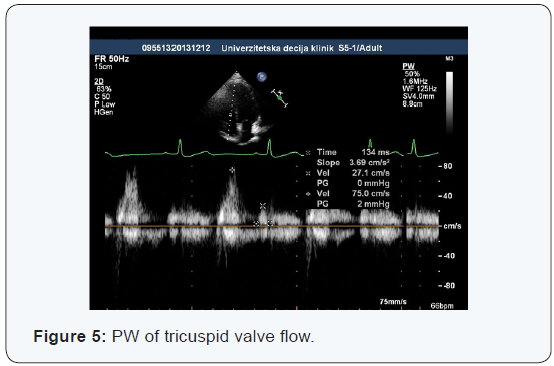

Doppler echocardiography tricuspid flow

The speed and the duration of individual phases of tricuspid inflow are a good indicator of right ventricular diastolic function, that is, its relaxation and diastolic pressures. Two speeds are analyzed on the spectrogram (early –E, and late - A diastolic inflow) and two intervals (isovolumic relaxation time - IVRT and diastasis). The spectrogram of tricuspid inflow shows certain changes during respiration which are considered normal. From inspiration to expiratory flow, the speeds of tricuspid inflow increase, the early E inflow for about 25%, and late A inflow for about 20%, and E / A ratio remains unchanged. Because of these changes, tricuspid inflow measurements by Doppler methods, must be defined and interpreted in relation to the phase of respiration in which they are made. The age of a child has no significant impact on the values of the tricuspid inflow parameters, except in the neonatal age, when the normal result is of higher speed of A waves compared to the E wave.

Normal functioning of the right atrium, tricuspid valve, as well as adequate compliance of the right ventricle is necessary for the adequate diastolic function of the right heart. With diastolic dysfunction, the first changes include the increase of function of the right atrium tank and pumps, while at later stage, conduit function dominates. At the same time, depending on the cause of diastolic dysfunction, there is a reduction of compliance and an increase in the right ventricle diastolic pressure. These changes are reflected in the spectrogram PW of Doppler tricuspid inflow. The state of hydration can also change the appearance of the tricuspid inflow spectral curve.

Our study showed tricuspid inflow speed values that fit into existing spectrogram models of a heart with normal function. Early diastolic tricuspid inflow was significantly of a higher speed compared to the late diastolic inflow during the atrial contraction (0.67 ± 0.15 m / s vs 0.44 ± 0.14 m / s) so that the average ratio of the early and the late diastolic inflow was 1.63 ± 0.5. In atrial contractions, the right ventricle was filling with blood on average 63.3 ± 35.1 ms longer than the inferior vena cava and hepatic veins, which corresponds to normal hemodynamic conditions.